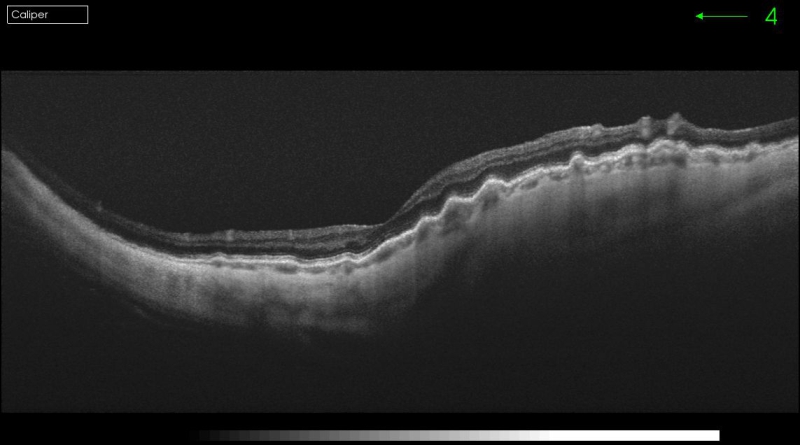

La angiografía fluoresceínica tiene un papel destacado en los pliegues de reciente aparición porque revela el patrón característico de hiperfluorescencia en las crestas combinada con hipofluorescencia en los valles (Figura 1). La tomografía de coherencia óptica (OCT) tiene una especial utilidad en diferenciar los pliegues coroideos de los pliegues retinianos secundarios a patología de la interfase vítreo-retiniana (Figura 2A y Figura 2B)3. Los últimos son más finos, irregulares y menos pigmentados; no se visualizan en la angiografía y la OCT revela su causa (membrana epirretiniana, tracción vítreo-macular…). Recientemente se ha demostrado que los grosores coroideos subfoveales medidos con OCT son mayores en los pacientes con pliegues en comparación con la población normal4. La autofluorescencia es una técnica útil y además no invasiva en la demostración del típico patrón que muestra la angiografía. Se diferencia de ella que el patrón de líneas claras y oscuras aparece de forma inversa (las crestas son hipoautofluorescentes y los valles hiperautofluorescentes)5.

Figura 2A. OCT-SD pliegues retinianos producidos por una membrana epirretiniana.

Figura 2B. OCT pliegues coroideos en el caso de una maculopatía por hipotonía en una cirugía filtrante de glaucoma.